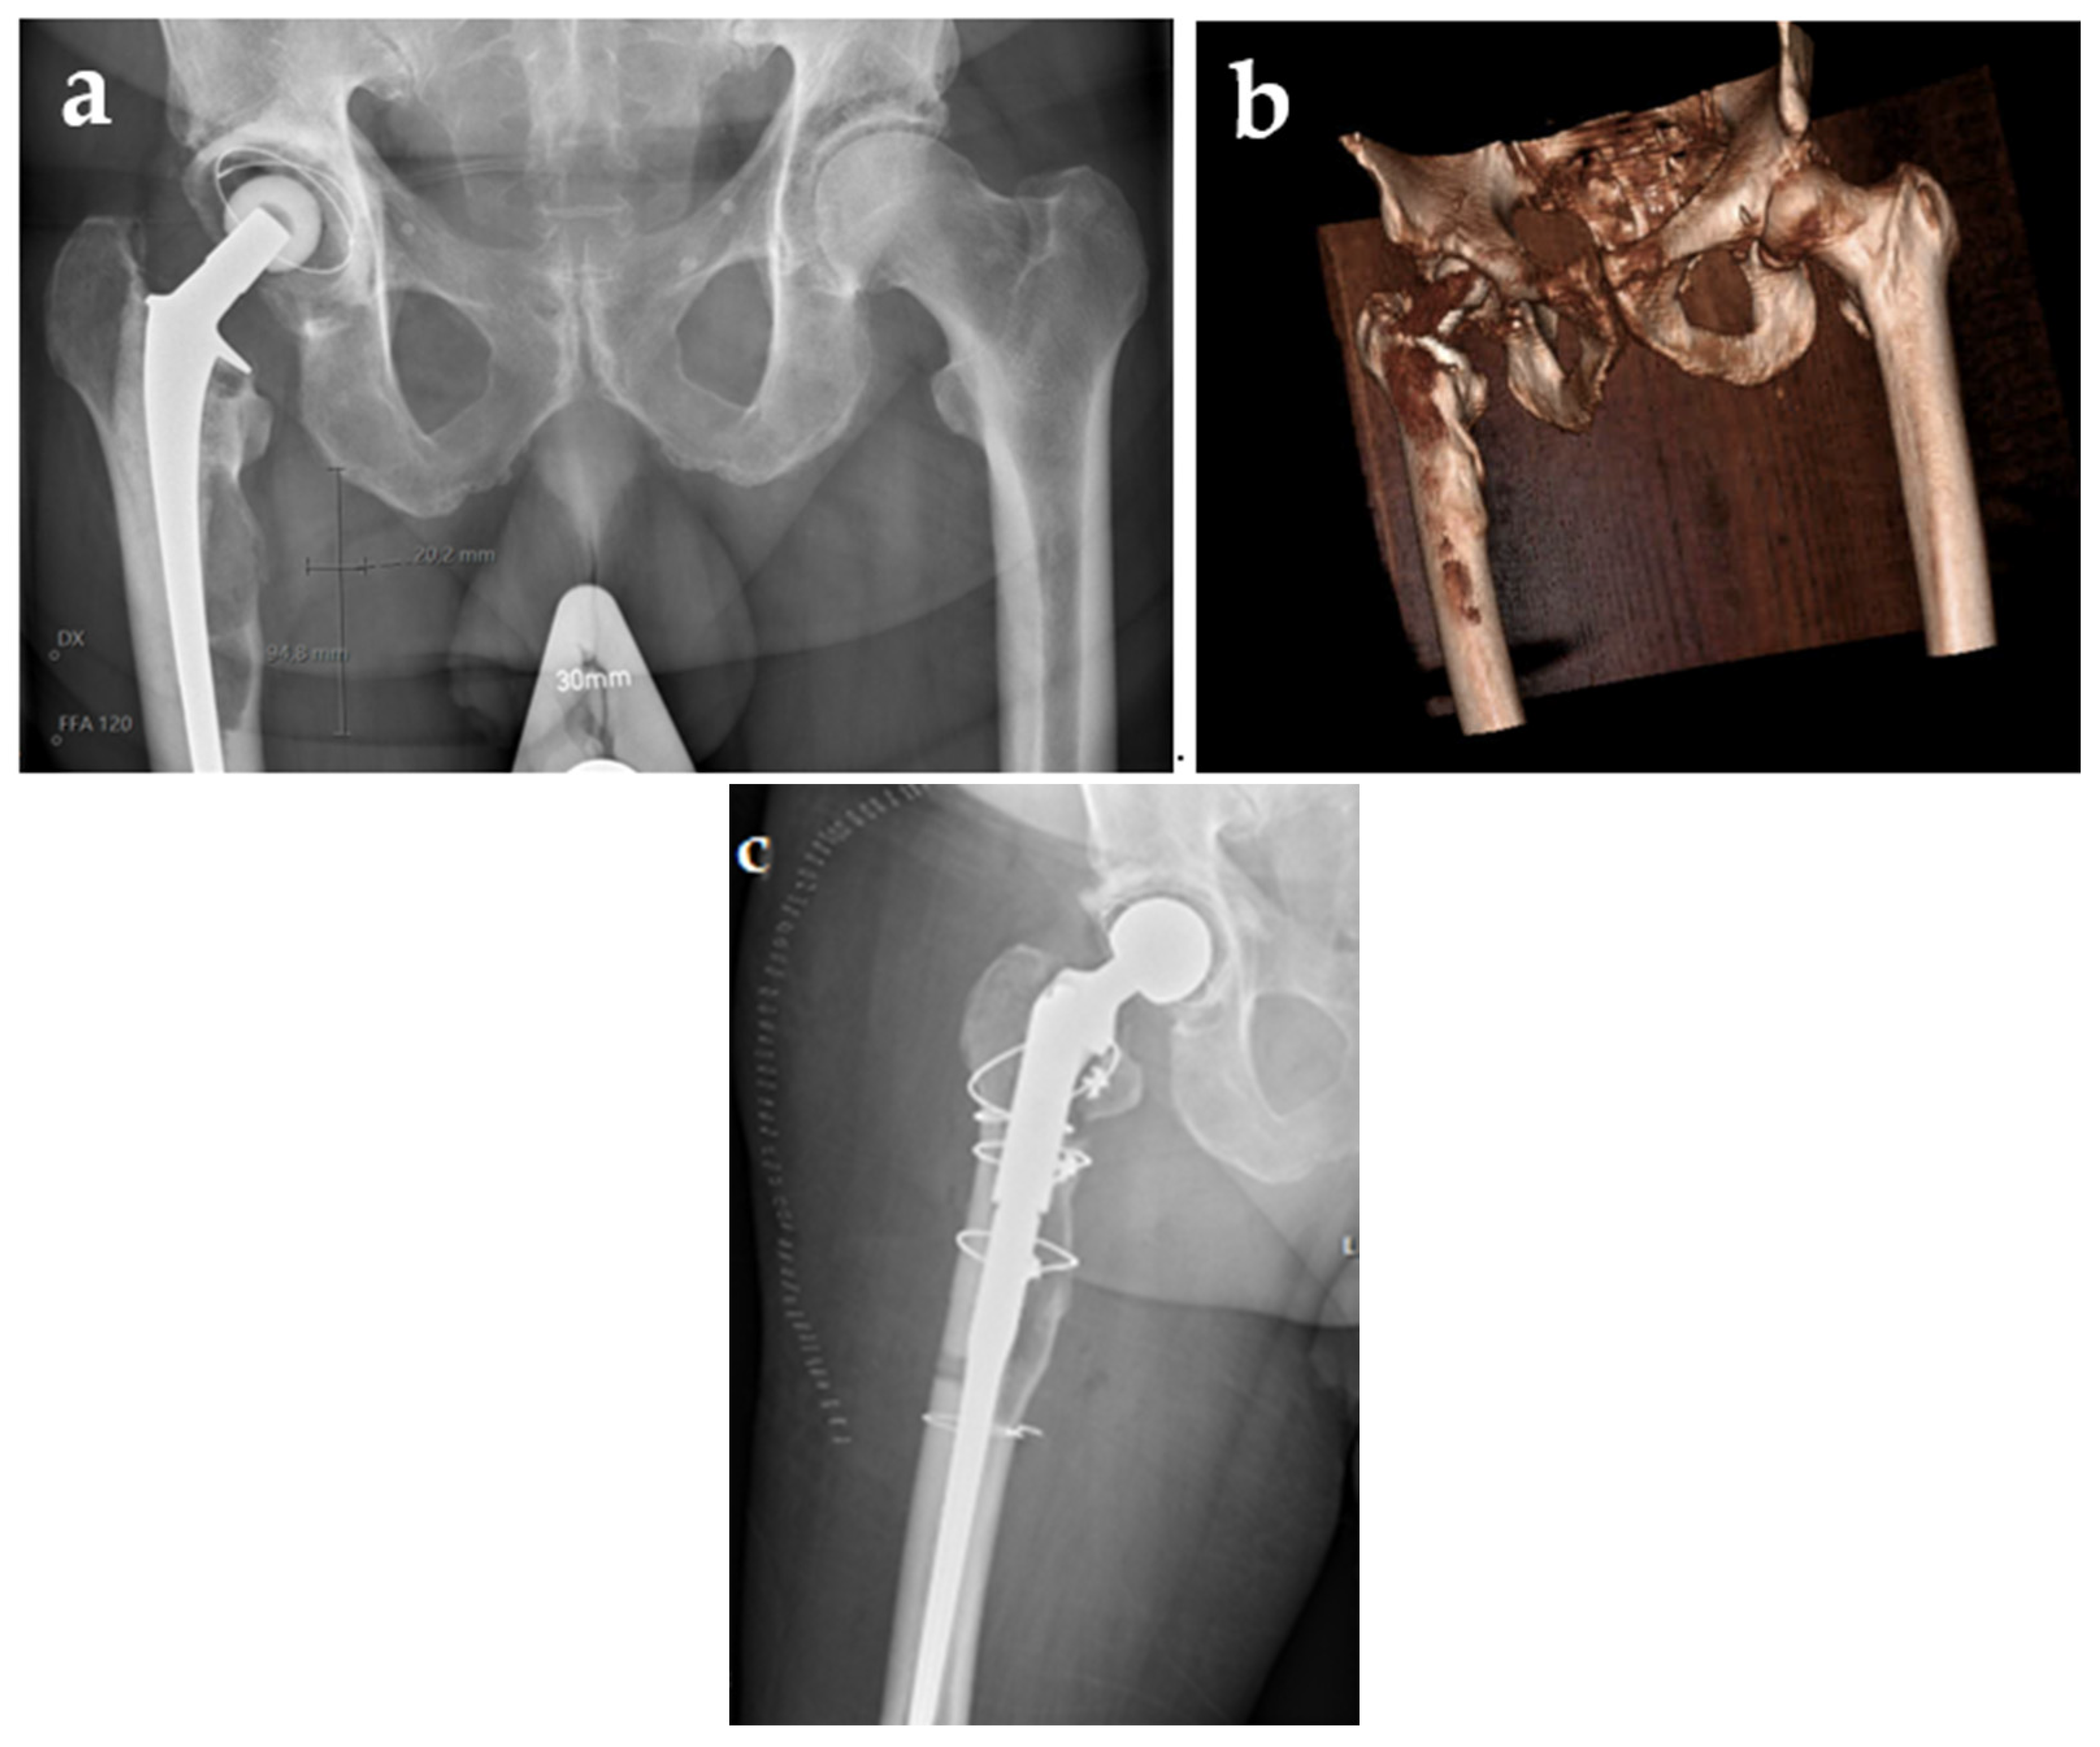

3.1. Clinical Course